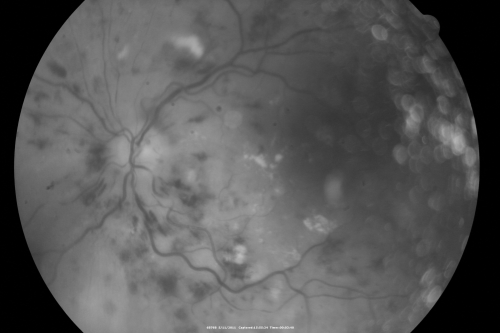

Malignany Hypertension - BP 250/130 - Vision 1/200 in each eye - Diabetic

68-year-old woman poor vision in both eyes for the last few years.  She is diabetic since 1989.  Her blood pressure has been very high.  She was in the hospital Friday.  Her blood pressure during that visit was 250/130 and her blood pressure in your office she reports was somewhere around the same.  I just checked her blood pressure at the beginning of my visit and it was 200/120 in her right arm sitting.  Her vision is poor enough that she can barely see to walk around.  She has also been feeling nauseous